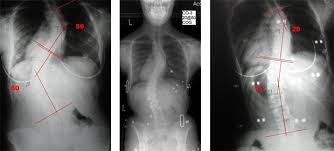

chair back support for scoliosis

cheap wedding chair covers ipswich See and discover other items: exercises for bad knees, scoliosis braces, sport wheelchairs, yoga black friday, office chair for bad back, yoga knee cushion